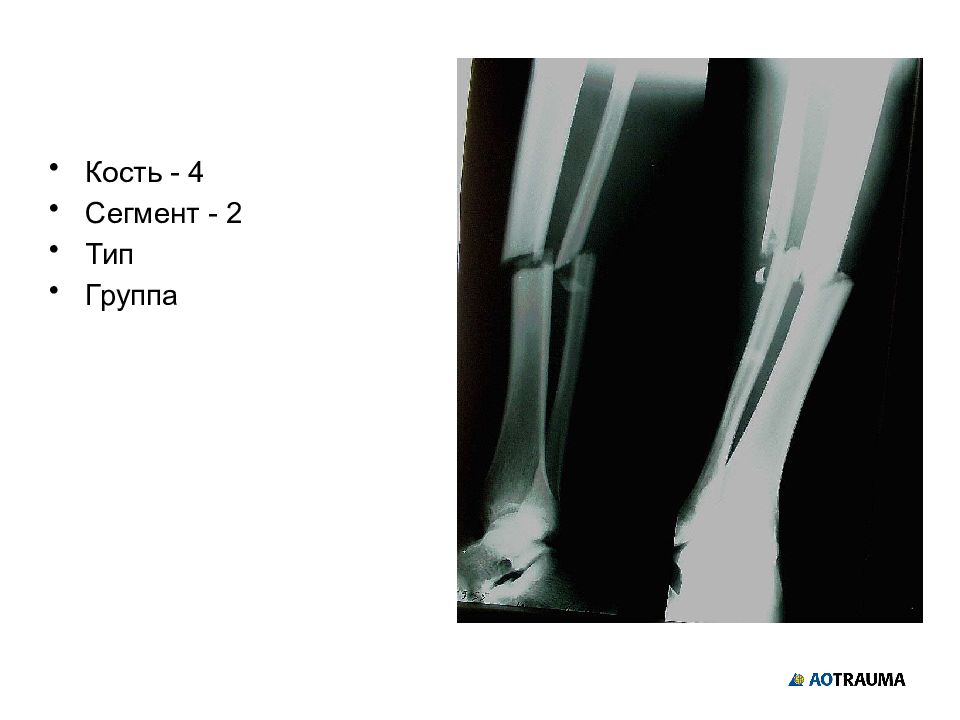

Кость - 4 Сегмент - 2 Тип Группа

Изображение слайда